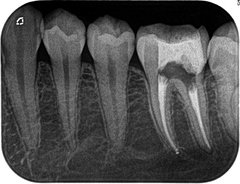

根管治療からセラミックのセットまでを2回の治療で。Part2 2017.02.01

根管治療からセラミックのセットまでを2回の治療で。Part1 2017.01.27